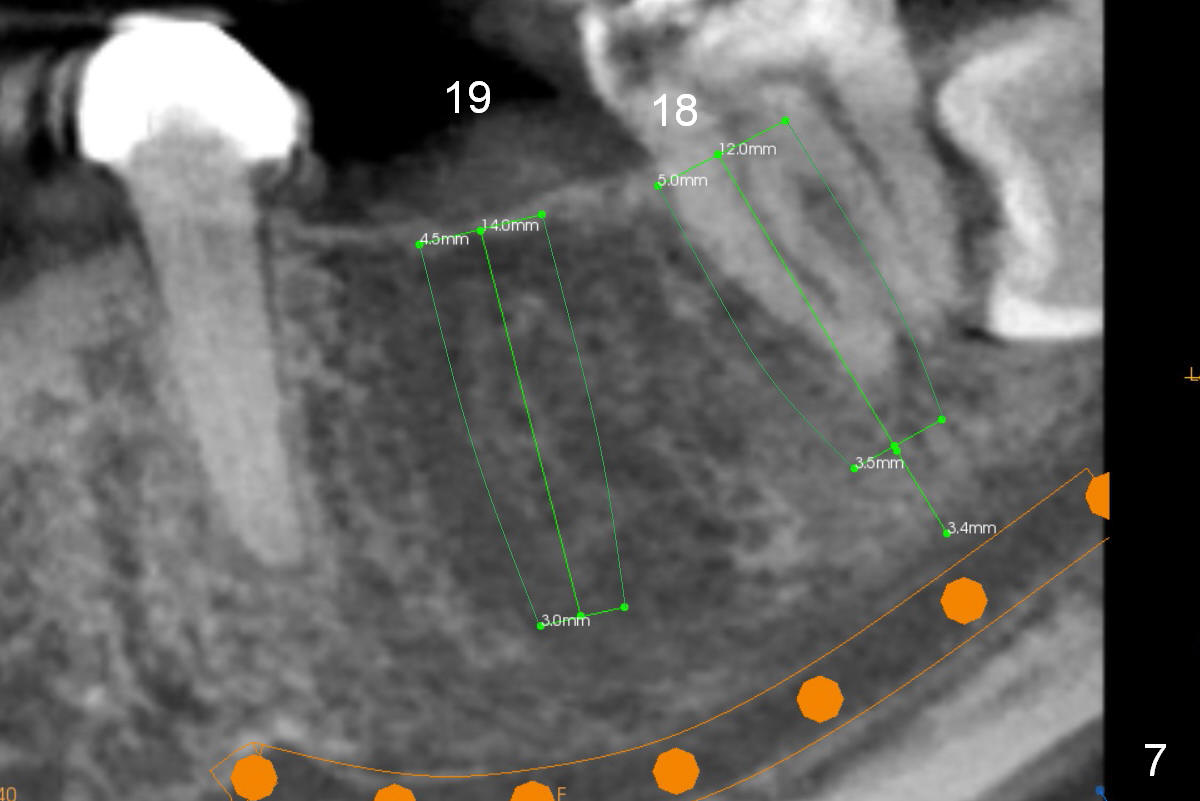

A 35-year-old lady (YL) has periodic nocturnal pain of the lower left quadrant.  There is open buccal margin at the abutment of #18 (Fig.1 (from panoramus)).  When the pontic and the retainer are removed (Fig.2), there is a large buccal subgingival carious lesion at the tooth #18.  The latter has 2 roots, although close to each other.  If the extraction turns out to be difficult, section the tooth (Fig.3 red line (no antibiotic)).  To avoid contacting the tooth #17, place an implant at the mesial socket of #18 (Fig.5,7).  Although it appears that the tooth #20 has no periapical radiolucency (Fig.6,7), the crown will be removed for diagnosis.  A 3-unit provisional will be fabricated after an implant is placed at #19 (Fig.7,8) in the same appointment.